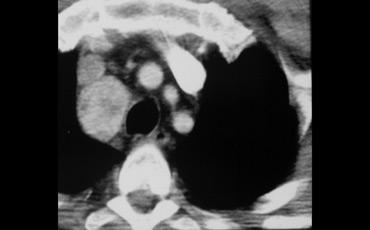

Hãy mô tả hình ảnh.

Sau đó tiếp tục.

Đầu tiên, lưu ý tuyến ức lớn ở trẻ nhỏ này.

Ngoài ra còn có một khối ngấm thuốc ở trung thất sau lan vào ống sống.

Đây là hình ảnh điển hình của u mạch máu (hemangioma).